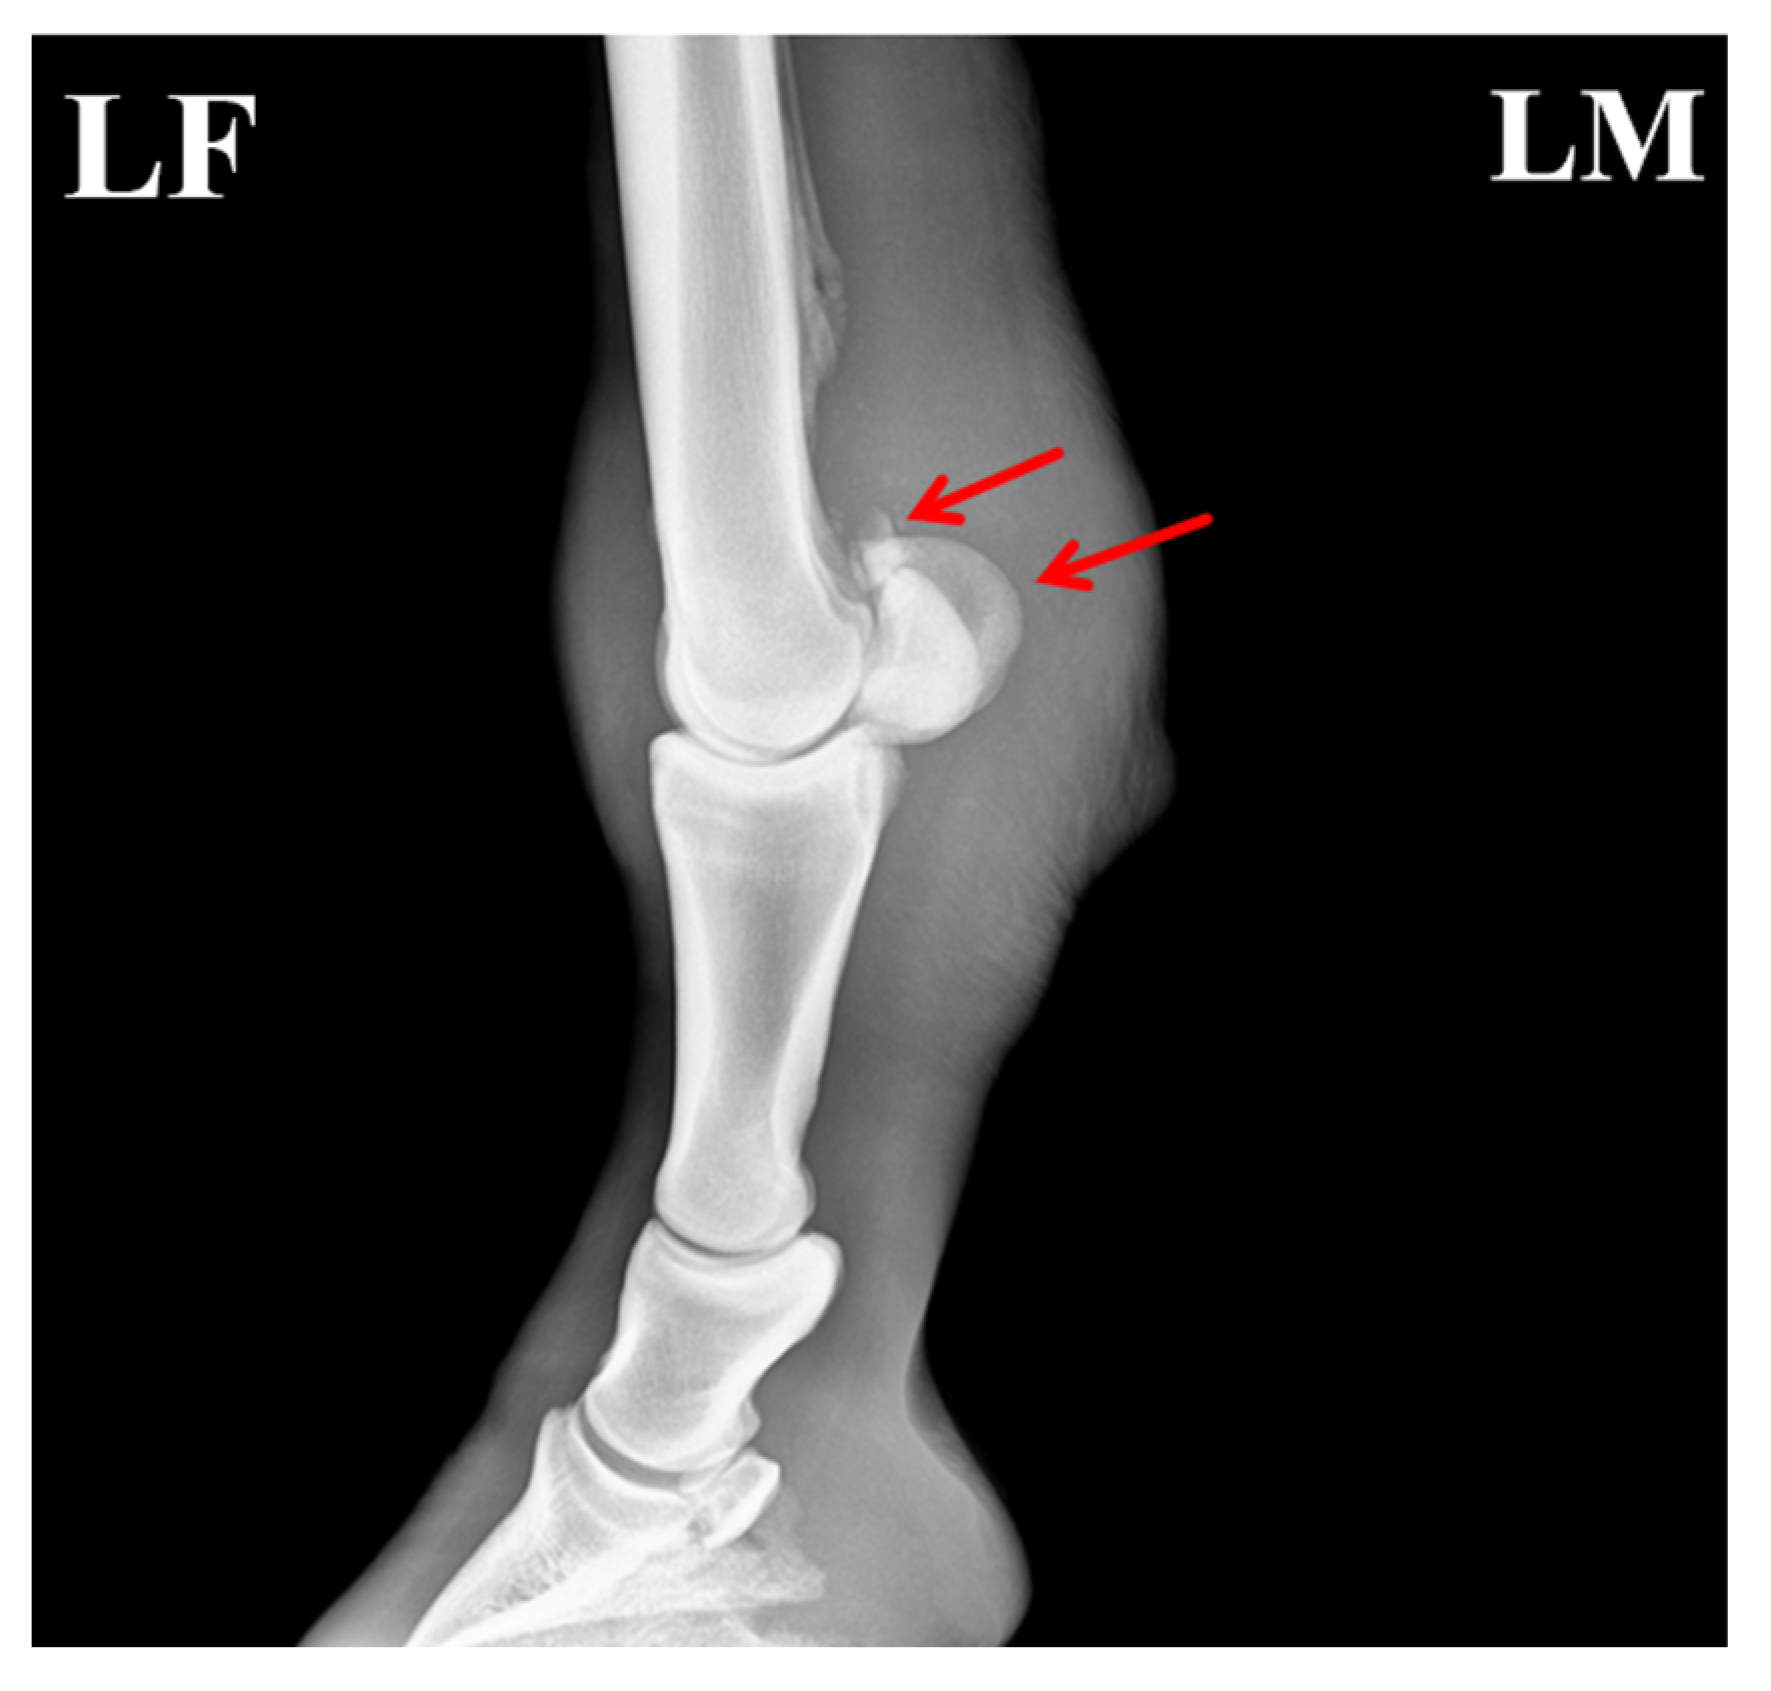

3.2.1. X-Ray Examination

Radiographic evaluation was performed to assess the type of lesion and to determine whether flexor tendinitis was present. Images were taken of the left forelimb (LF) in lateromedial (LM) and dorsopalmar/anteroposterior (AP) projections. The radiographs showed a clear fracture line at the proximal apex of the left proximal sesamoid bone, with separation of the fracture margins and the presence of a small free bone fragment. The fragment had an irregular shape and was displaced away from the main sesamoid body. Local cortical continuity was disrupted, and the trabecular pattern appeared disorganized. An increase in soft-tissue density was also noted in the flexor tendon region, raising suspicion of concurrent flexor tendinitis (Figure 2).

Figure 2. Radiographic features of the affected horse with PSBF. (A) Fracture at the apex of the proximal sesamoid bone (red arrow: bone fragments; blue arrow: increased radiodensity in the flexor tendon region). (B) Fracture fragments of the proximal sesamoid bone. The arrows indicate the specific lesions.